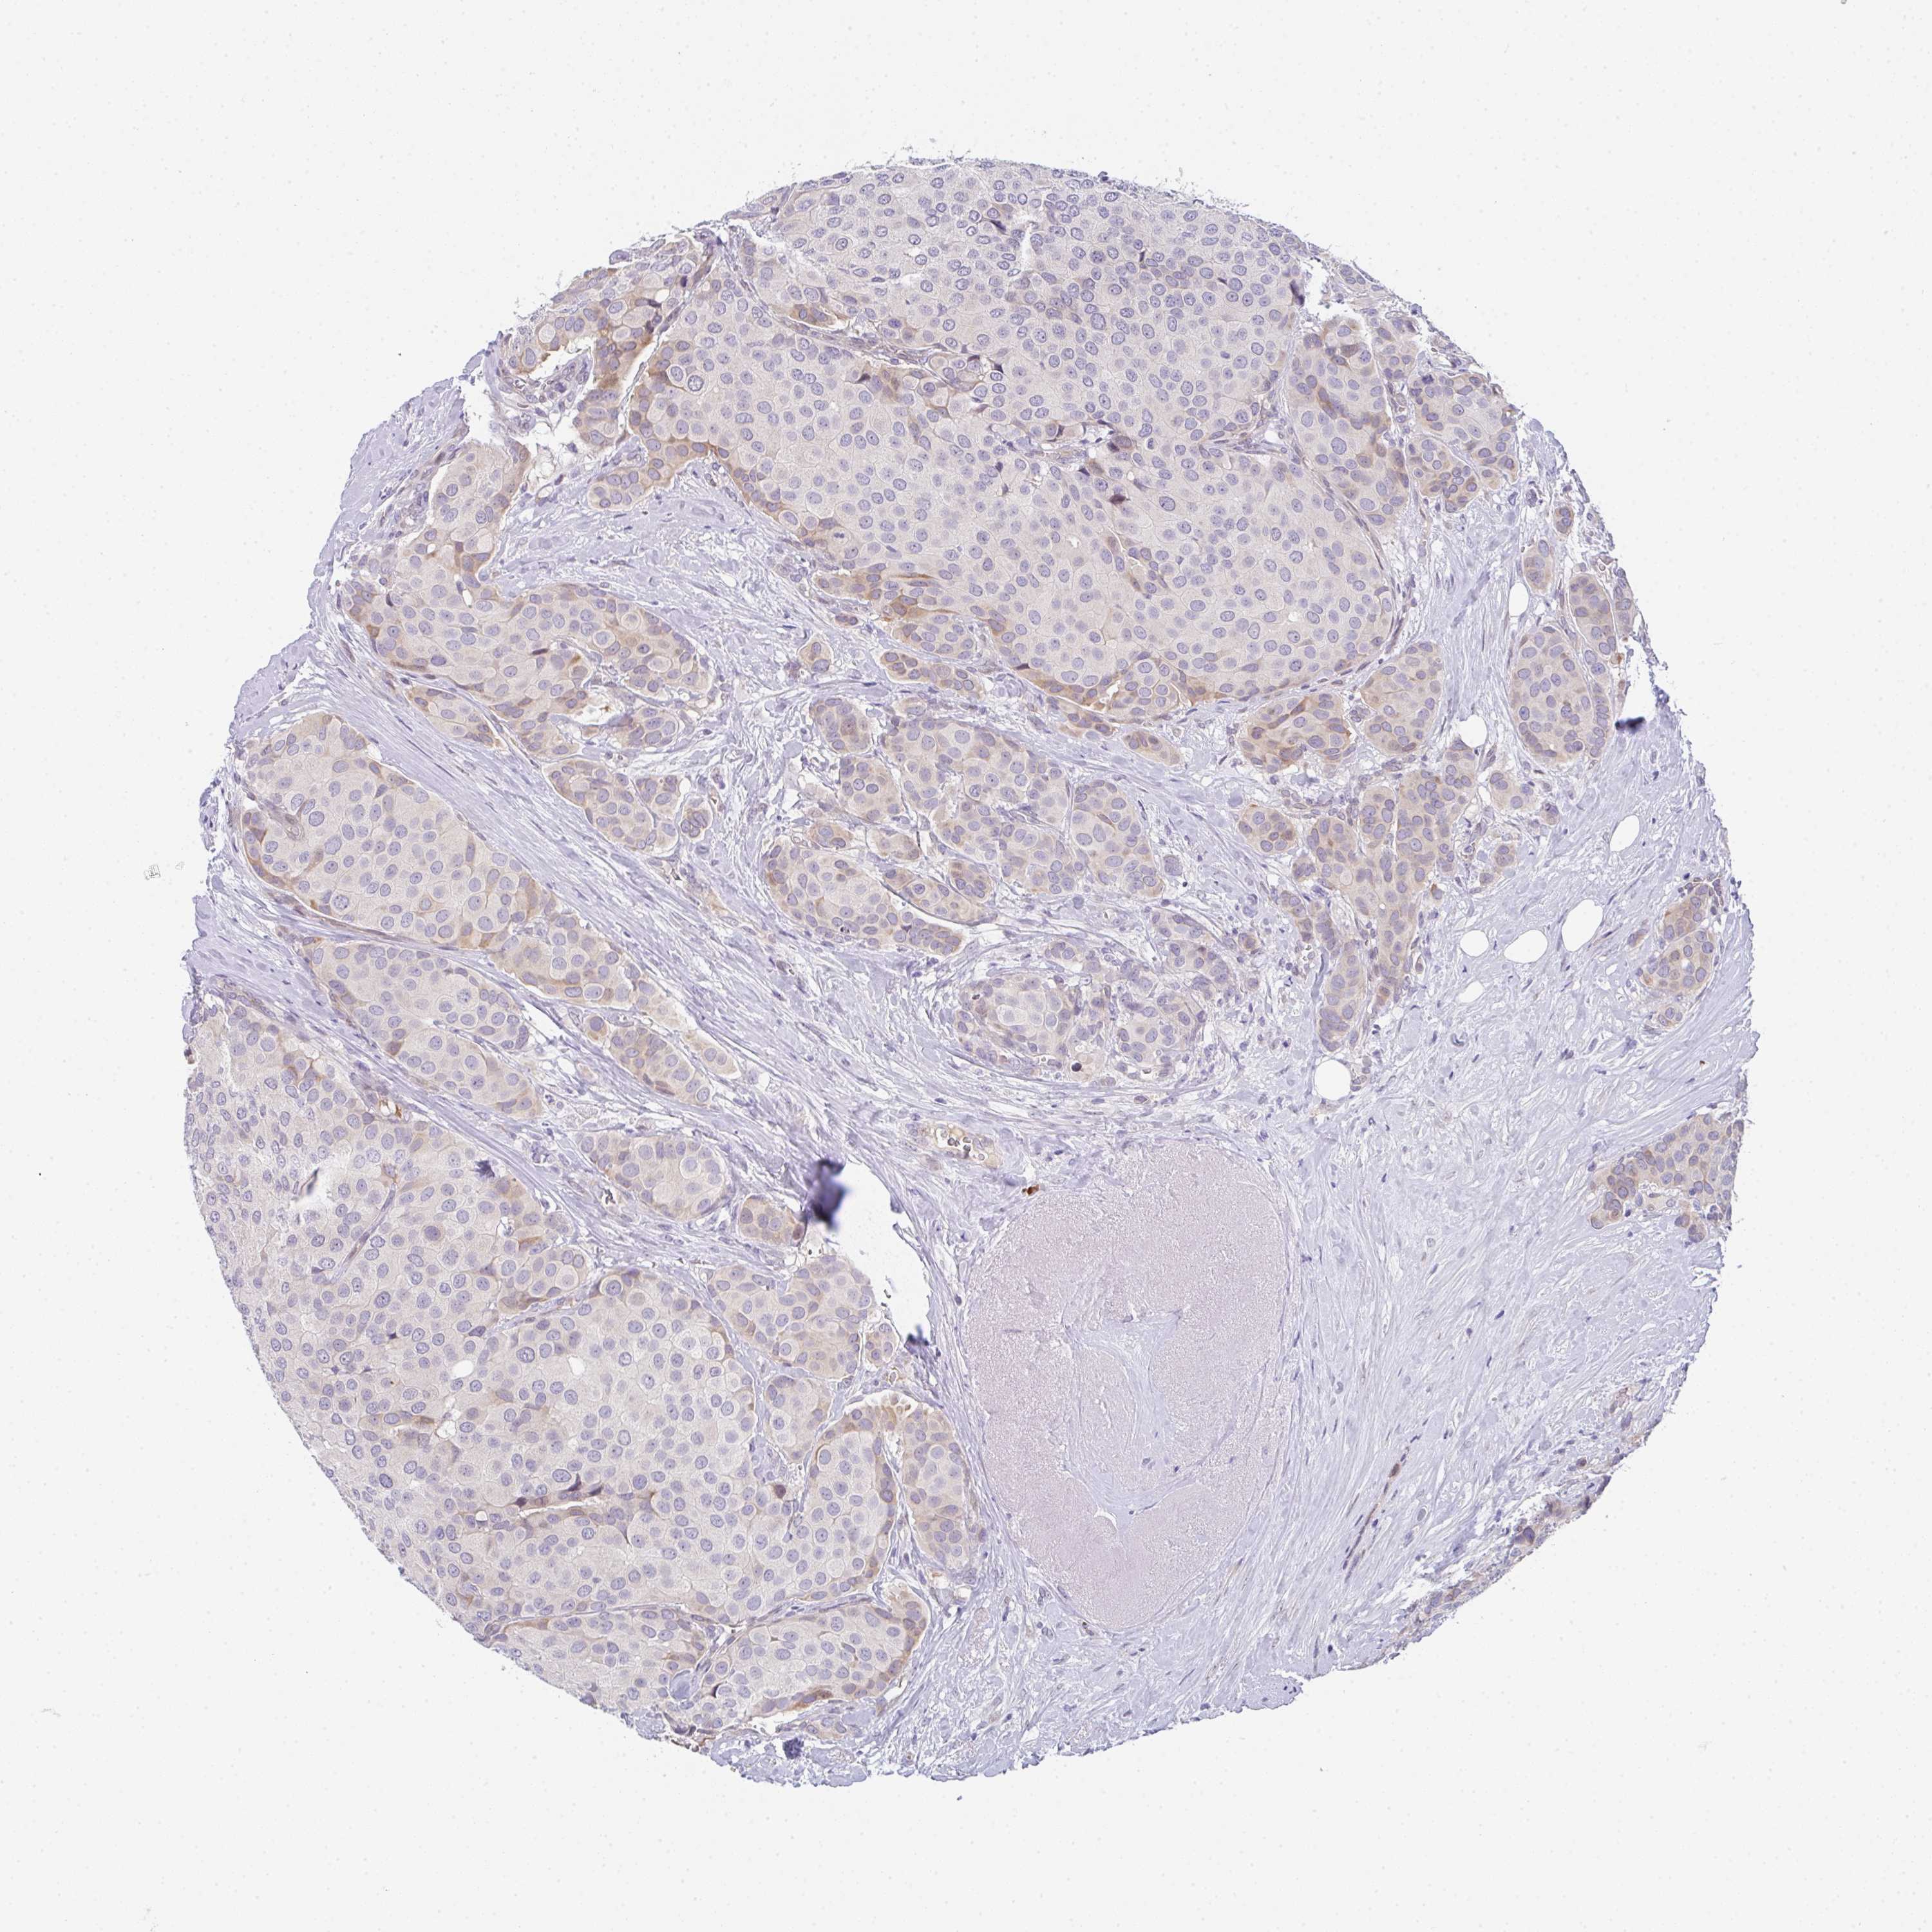

BRCA TCGA BRCA VALIDATION PROTEIN EXPRESSION